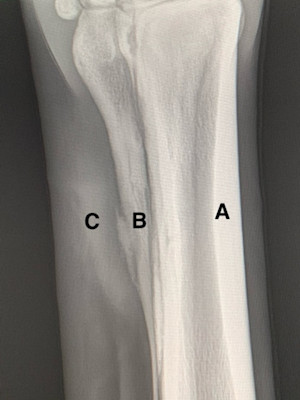

Discovered in 1895, x-rays are used to image internal organs and bones. X-rays are created by a generator and form a beam that passes through the area of the horse’s body being examined. As the x-rays pass through, different tissues absorb them at different levels. Dense tissues, like bone, only allow for small amounts of x-rays to pass through, resulting in whiter areas. Soft tissues let more x-rays pass through, which then appear as darker areas. The x-rays that do pass through are recorded by a digital plate called a detector. In the past this would have been done on film, much like taking a picture.

Most x-ray exams can be done at the barn and without sedation. The most common use of radiography is to image the legs, hooves, back, and neck, often in cases involving lameness or injury. Here are some examples of when x-ray may be used:

- X-rays of the feet could help your farrier with trimming and shoeing for optimal foot balance (Fig. 2).